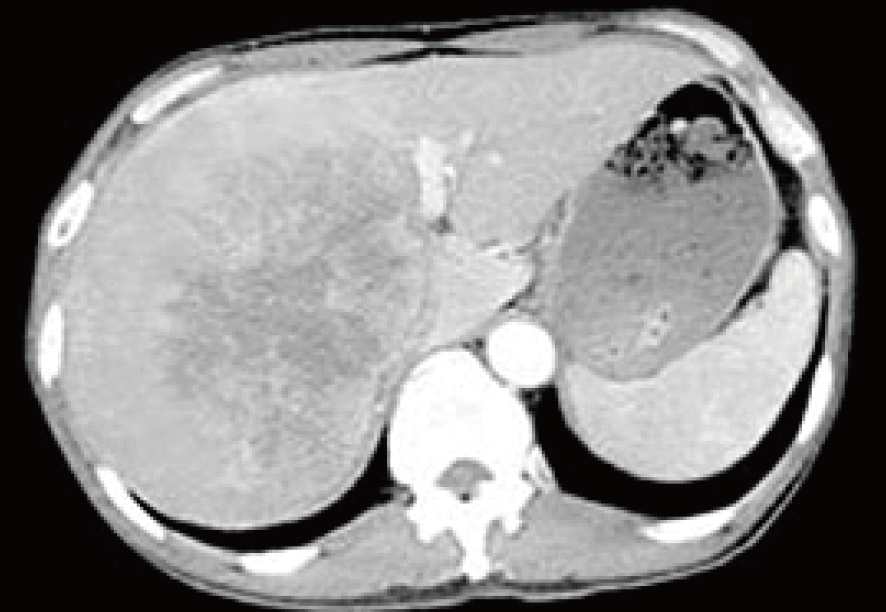

治療前CTでは肝臓の右葉に広がる肝転移病巣を認めている。

上記治療(内服6ヶ月・点滴4回)を行い、およそ4ヶ月経過時点のCTを示す。肝臓の大部分を占めた転移がんに壊死(黒色に変化した部分)が生じ、その部分でのがん活動性はほぼ消滅。引き続き再発防止の観点から定期的経過観察を指示。